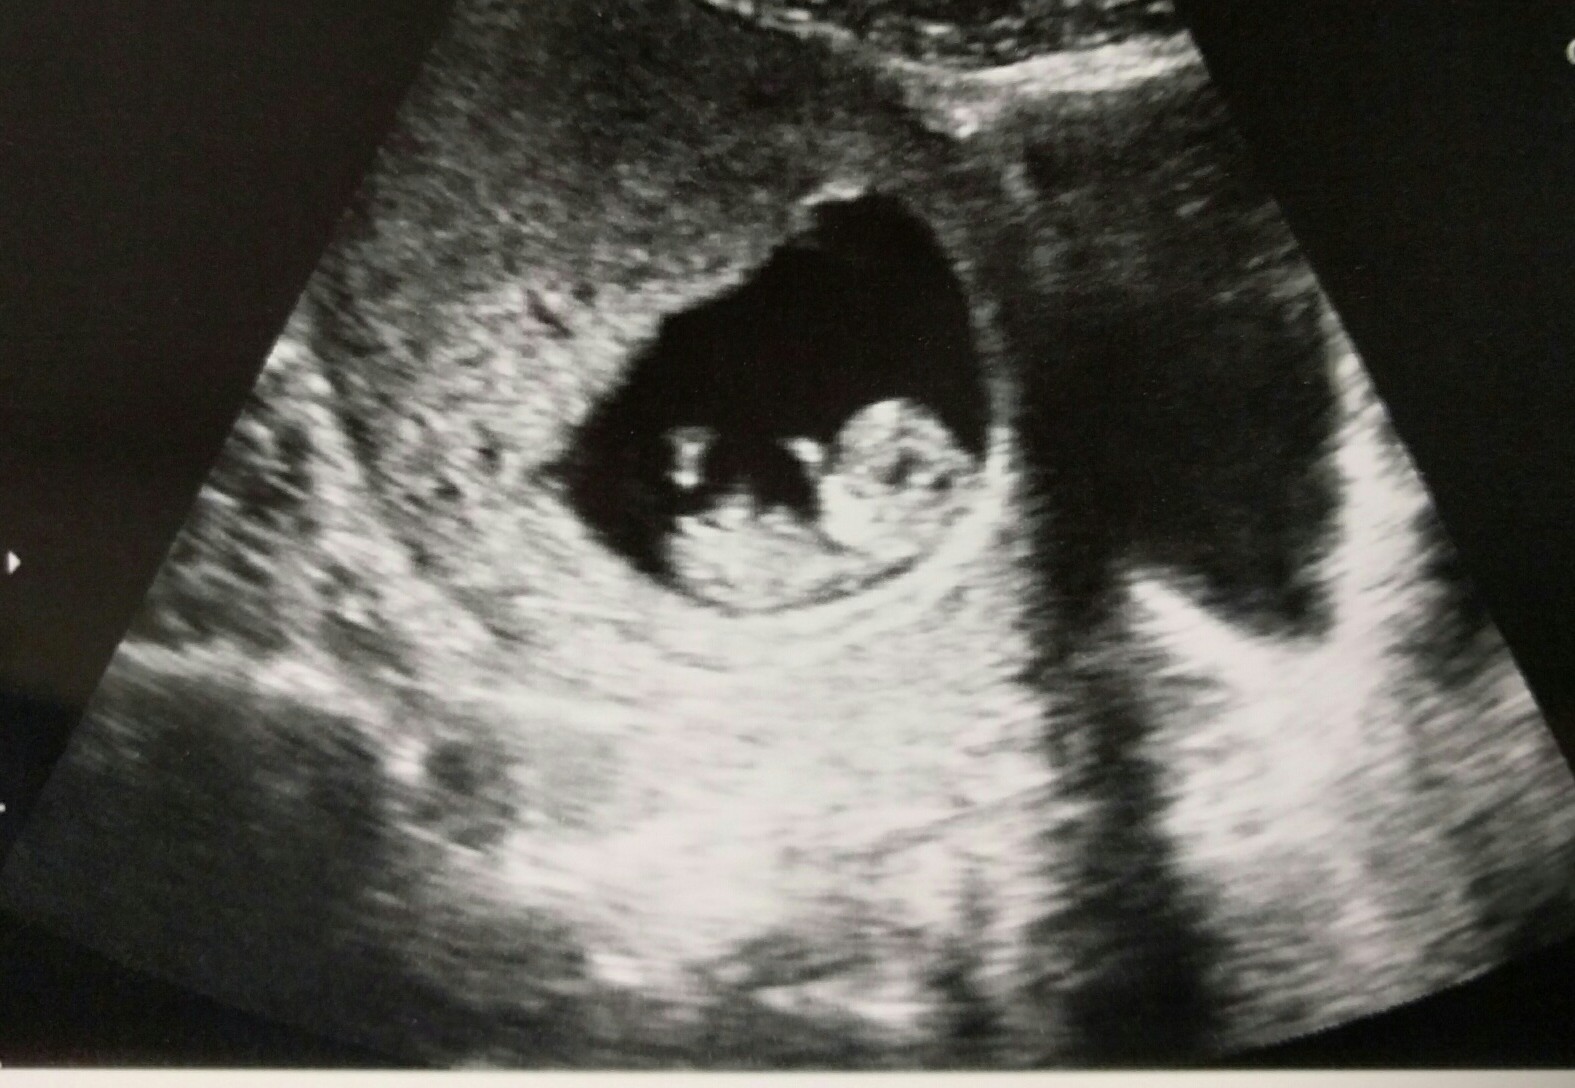

Had our first scan today at 9w5d HB 178!! My OB had trouble with the machine so the measurement is a little smaller than what baby really is, going for NT scan in a few weeks